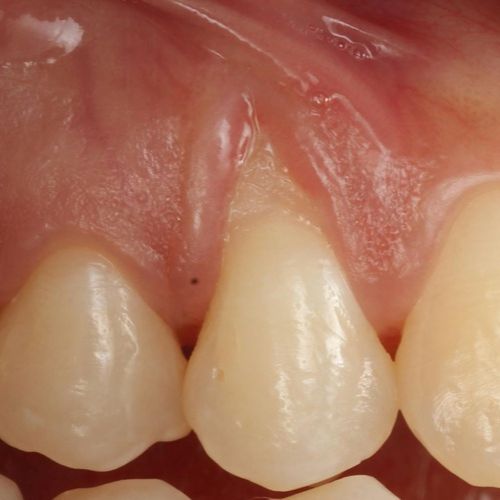

| Before and after surgery to reshape gums | X-ray showing results before and after bone graft surgery |

| Free gingival graft surgery’ to thicken gum and prevent further recession | Gum recession surgery in an aesthetic site |